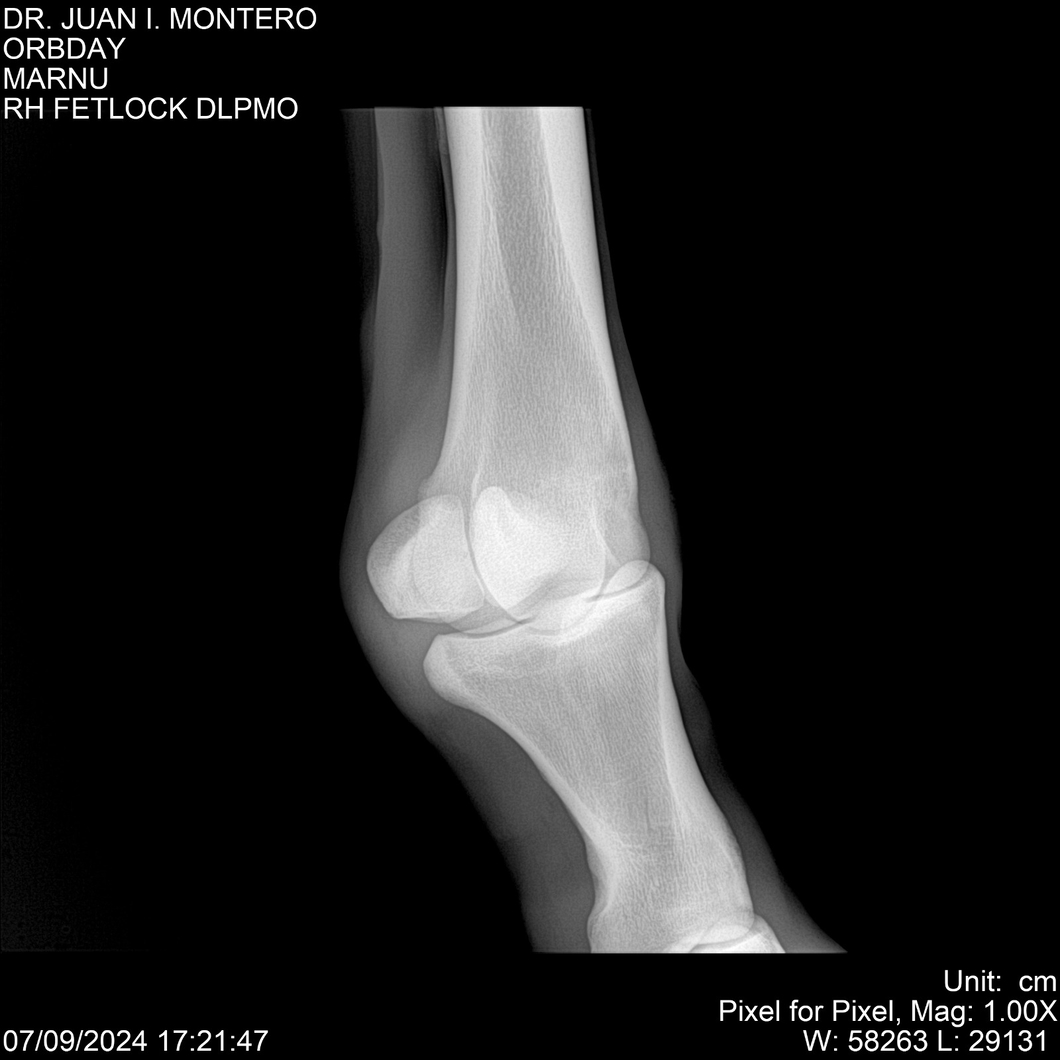

• Empresa: Abelenda N. R., Walter Hugo